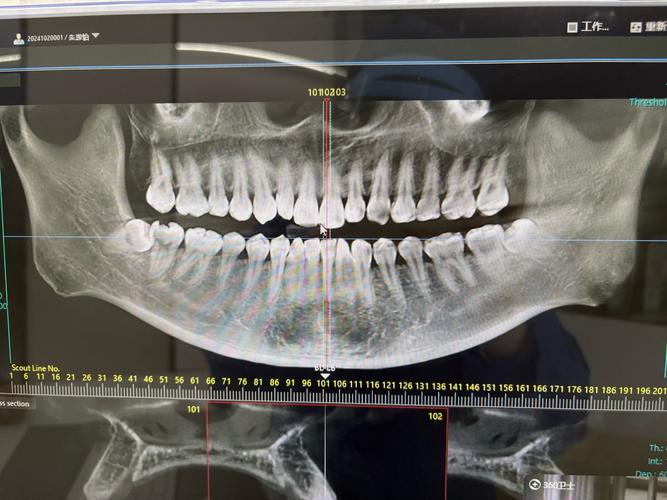

从临床角度看,CT在牙齿矫正中主要解决传统二维X光片难以呈现的复杂问题,当患者存在埋伏牙(牙齿未能正常萌出,被骨或软组织包裹)时,全景片只能显示牙齿的大致位置,而CT能通过三维重建清晰呈现埋伏牙的方向、深度、与邻牙及牙根的关系,判断是否需要手术助萌或是否会影响矫正进程,再比如,部分患者可能存在牙根吸收、弯曲或牙根形态异常,这些细微变化在二维影像中可能被重叠或忽略,而CT能多角度观察牙根情况,避免矫正过程中因牙齿移动加重牙根损伤。

骨量评估也是CT的重要应用场景,对于需要种植支抗(将种植体作为牙齿移动的“锚点”)或正颌手术(矫正严重骨性畸形)的患者,医生需精确了解牙槽骨的厚度、密度以及重要解剖结构(如下牙槽神经管)的位置,CT的三维成像能提供精准数据,确保支钉植入或手术的安全,若患者存在颞下颌关节(TMJ)问题,如关节弹响、疼痛或张口受限,CT可观察关节骨结构是否异常,帮助判断关节问题是否与矫正方案冲突。

并非所有矫正都需要拍CT,对于简单的牙齿排列问题,如轻度拥挤、散 gap,且无明显骨性异常、埋伏牙或关节症状,全景片和头颅侧位片通常能满足需求,这两种二维影像能清晰显示全口牙齿形态、牙槽骨情况以及上下颌骨的相对位置,帮助医生分析牙齿拥挤度、 Spee曲线深度、面部突度等基础指标,制定常规矫正方案,对于儿童青少年,若处于替牙期且无明显复杂问题,医生可能先通过定期观察和二维影像监测,暂不进行CT检查,以减少辐射 exposure。

| CT(三维重建) | 牙根、骨量、埋伏牙、关节 | 多平面观察,精准定位,三维立体呈现 | 辐射较高,费用较高 | 复杂病例(埋伏牙、牙根异常、正颌手术) |